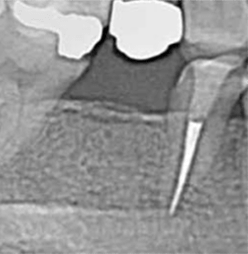

症例4【50代女性】左上6 副鼻腔膜を挙上しインプラント埋入 左上5 歯根破折の為インプラント埋入

治療前

左上5の歯根破折

主訴 左上奥歯で物が噛めない。入れ歯は煩わしいので、インプラントを希望。

左上第一大臼歯欠損部位は、骨の高さが3~4㎜しかなく、造骨の為にソケットリフト(骨造成)を行い、骨の高さを確保しインプラントを埋入。

約半年の免荷期間を経て、仮歯を装着、リハビリをし、約7ヶ月後にメタルボンド(金属焼付ポーセレン)を装着。

その後、左上第二小臼歯の歯根破折の為に、2本目のインプラントを埋入。(抜歯即時埋入)

リスクとしては、ソケットリフト(骨造成)による一過性の副鼻腔炎が起きる可能性がある。まれに洞底膜が破れる可能性がある。ただし、膜は約3週で再生するので、膜の回復を待ち、再オペを行う。

費用 111万(オペ。ソケットリフト・人工骨・採血による濃縮血小板生成・仮歯・最終補綴物まで含む)